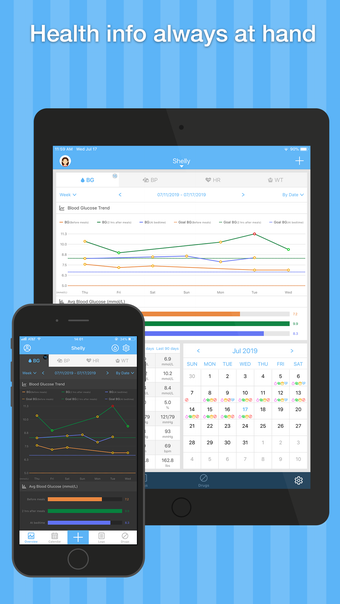

Kan Basıncı Glukoz Pal, iPhone için ücretsiz bir programdır ve 'Tıp' kategorisine aittir.iPhone için Kan Basıncı Glukoz Pal Hakkında

Kan Basıncı Glukoz Pal, iOS 16.4 veya üzeri gerektirir. Programın mevcut sürümü 5.1'dir ve Almanca, Fransızca ve Rusça olarak edinebilirsiniz.